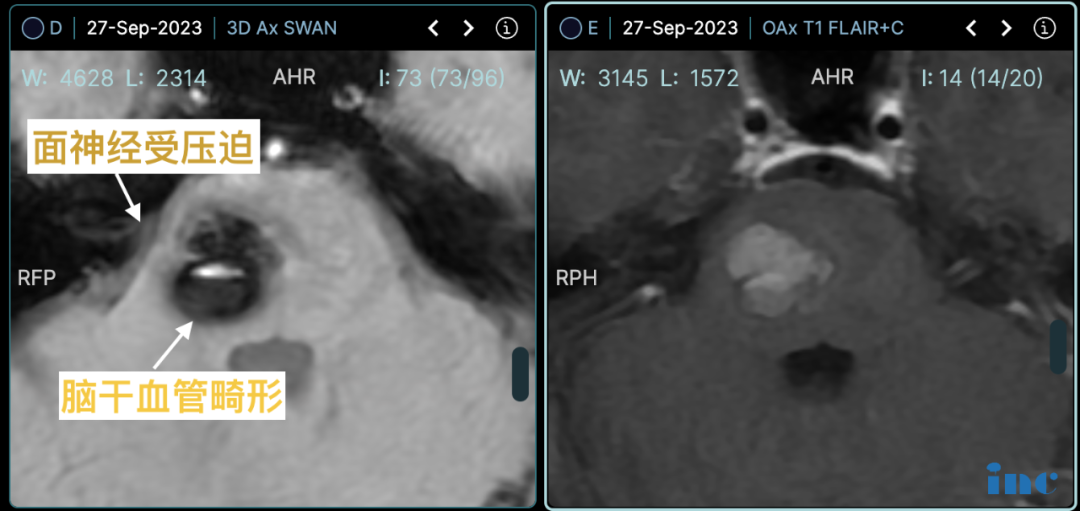

患者在上海多家医疗机构咨询后,获得继续观察随访的建议。为寻求积极治疗方案,患者家属通过多方渠道了解到擅长脑干区域手术的巴特朗菲教授。经过远程咨询评估,巴特朗菲教授认为虽非急诊手术,但建议尽早干预,以预防不可预见的神经功能损伤。手术方案设计同时解决脑干海绵状血管瘤和面神经血管压迫两个问题。